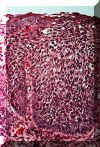

En algunos casos las anormalidades

celulares son tan severas y la maduración del epitelio muy pobre, que

el espesor entero del epitelio no hay diferencia entre la capa basal y

la superficie. Cuando ocurre esto la lesión se designa carcinoma in

situ. Todavía no hay infiltración en el tejido conjuntivo. |